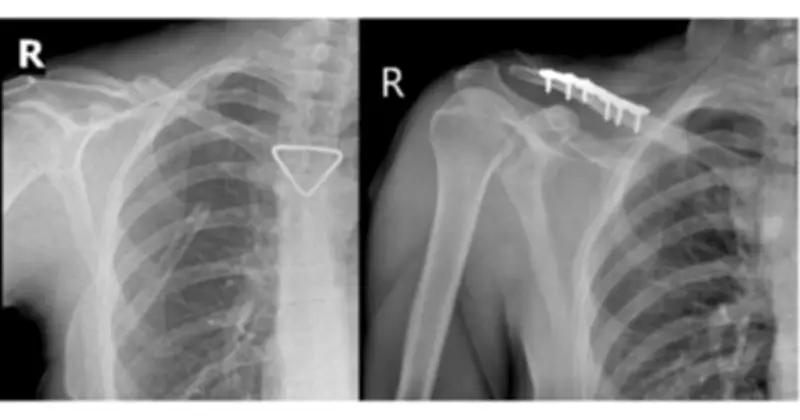

Ca mổ do ê-kíp Bác sĩ chuyên khoa II Trần Văn Dương và Bác sĩ Phạm Ngọc Huy thực hiện, diễn ra thuận lợi. Nẹp vít được đặt vững chắc, trục xương phục hồi giải phẫu tốt, như minh chứng qua hình ảnh X-quang trước và sau mổ.